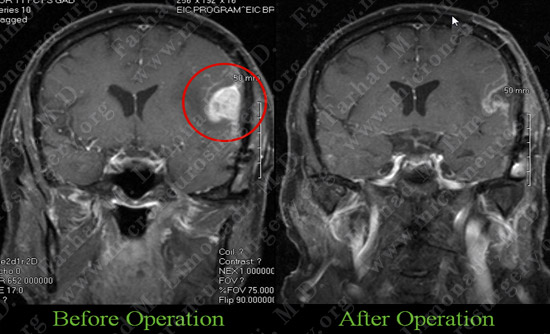

Post-op Imaging

Post-op MRI shows complete resection of the tumor with no injury to surrounding neurovascular structures